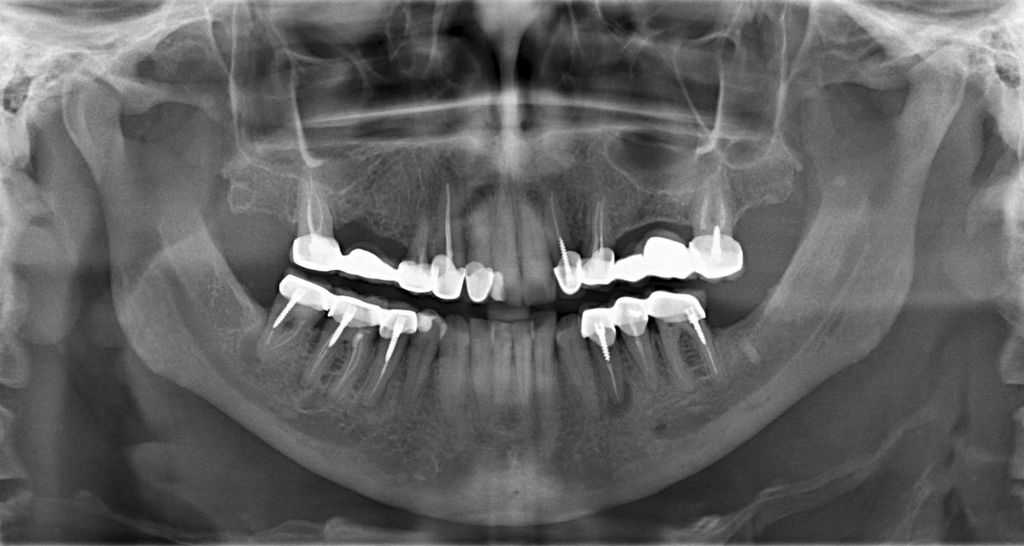

Можно ли делать МРТ со штифтами в зубах и металлокерамика: советы, фото

Точным и информативным методом исследования является магнитно-резонансная томография. Но этот метод диагностики имеет свои ограничения. При назначении процедуры возникает вопрос, можно ли делать МРТ со штифтами в зубах или коронками из металла.

МРТ при наличии штифтов

Магнитно-резонансную томографию делают для выявления заболеваний, особенно на ранних стадиях. Для этого аппарат делает серию снимков – срезов определенного внутреннего органа. Нужно очень высокое качество изображения, чтобы специалист мог обнаружить наличие дефектов в заданной области.

Если у пациента есть штифт в ротовой полости, он должен сообщить об этом перед проведением обследования. Можно ли делать МРТ со штифтами в зубах, будет решаться в зависимости от многих факторов:

В карточке описано, из какого материала сделан штифт. С полным описанием можно будет прийти на МРТ. Если нельзя сделать магнитно-резонансное обследование, то проводится компьютерная томография.